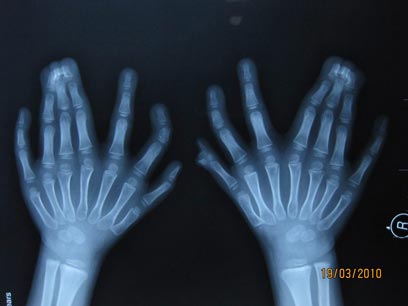

צילום רנטגן של אצבעות הידיים, חלקן דבוקות (צילום: AP)